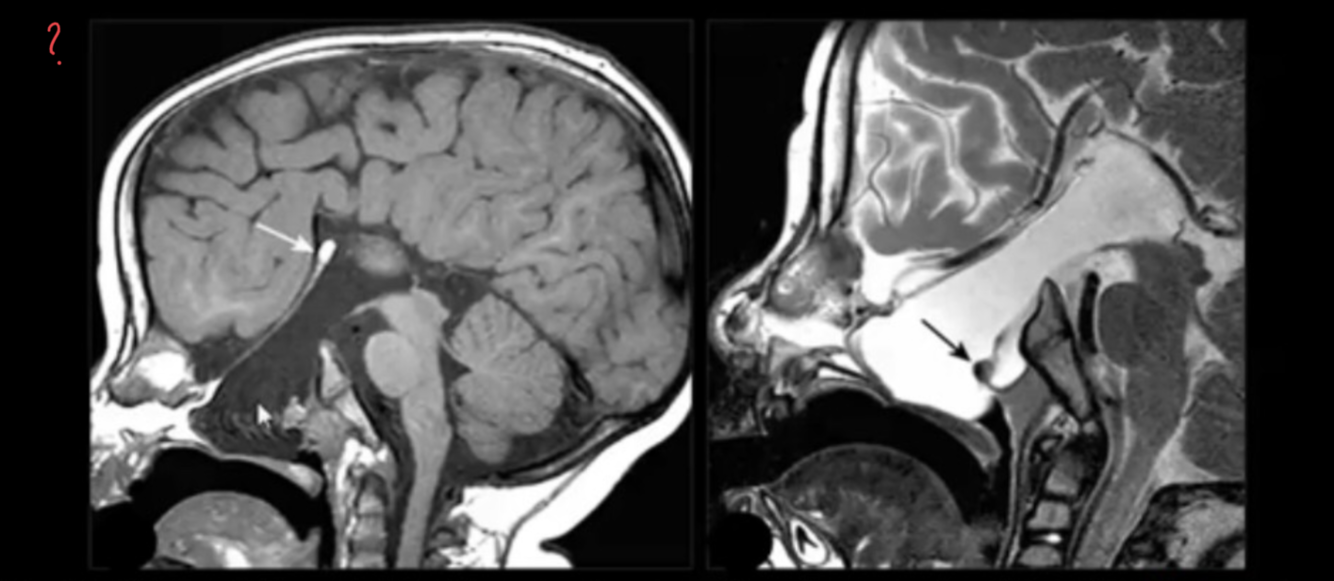

Description and dx?

?

ATTENTION

No continuation with intracranial compartment!

Different from encephalocele!!!